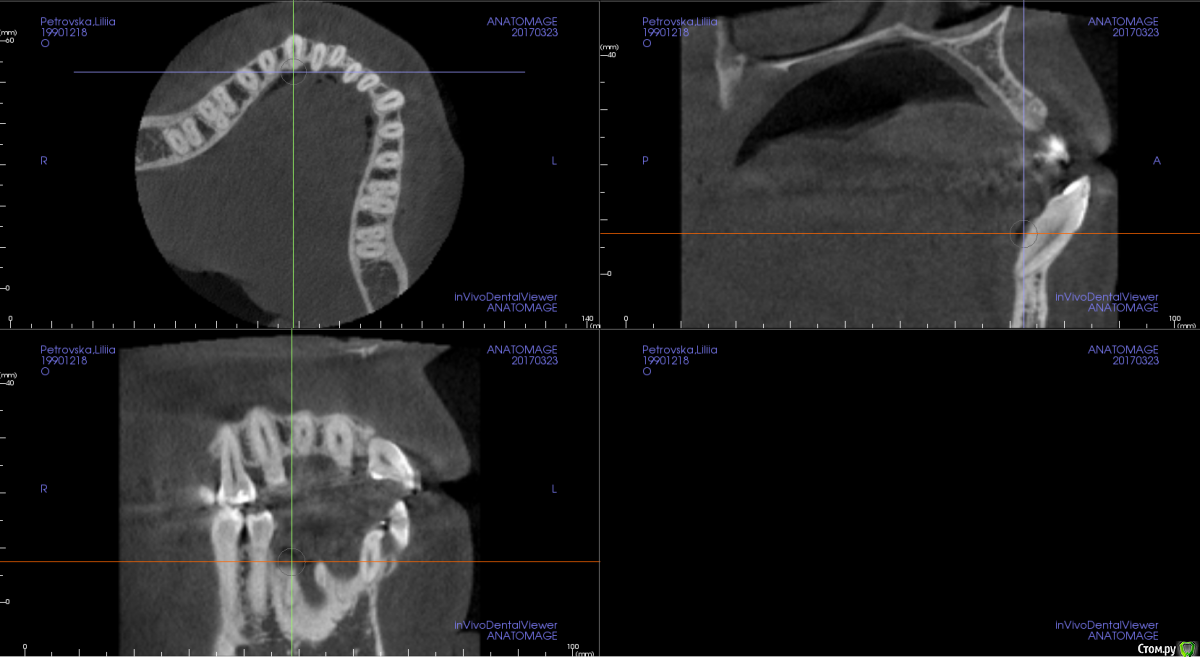

Opdihatop Опубликовано 4 марта, 2017 Поделиться Опубликовано 4 марта, 2017 И снова здравствуйте, коллеги. Вот такой вот случай к рассмотрению. Много лет назад пациентка уже проходила "камуфляжное" лечение. Со слов пациентки оно было закончено с передним открытым прикусом. Сейчас ситуация такая. Пациентка думает над ортохирургией, но меня смущает фронт н/ч. И по снимкам и по ситуации во рту корни 32, 31, 42, 43 зубов фенестрировали лингвальную кортикалку почти на всем протяжении, 33 - вестибулярную. Вопрос вот в чем: что делатьс этими зубами? Возможно ли их поставить на место? Или лучше не трогать, дольше простоят? Ссылка на комментарий

m.d.n Опубликовано 20 марта, 2017 Поделиться Опубликовано 20 марта, 2017 срезы кт покажите . на чем остановились Ссылка на комментарий

Opdihatop Опубликовано 26 марта, 2017 Автор Поделиться Опубликовано 26 марта, 2017 Прошу:313233414243 Ссылка на комментарий